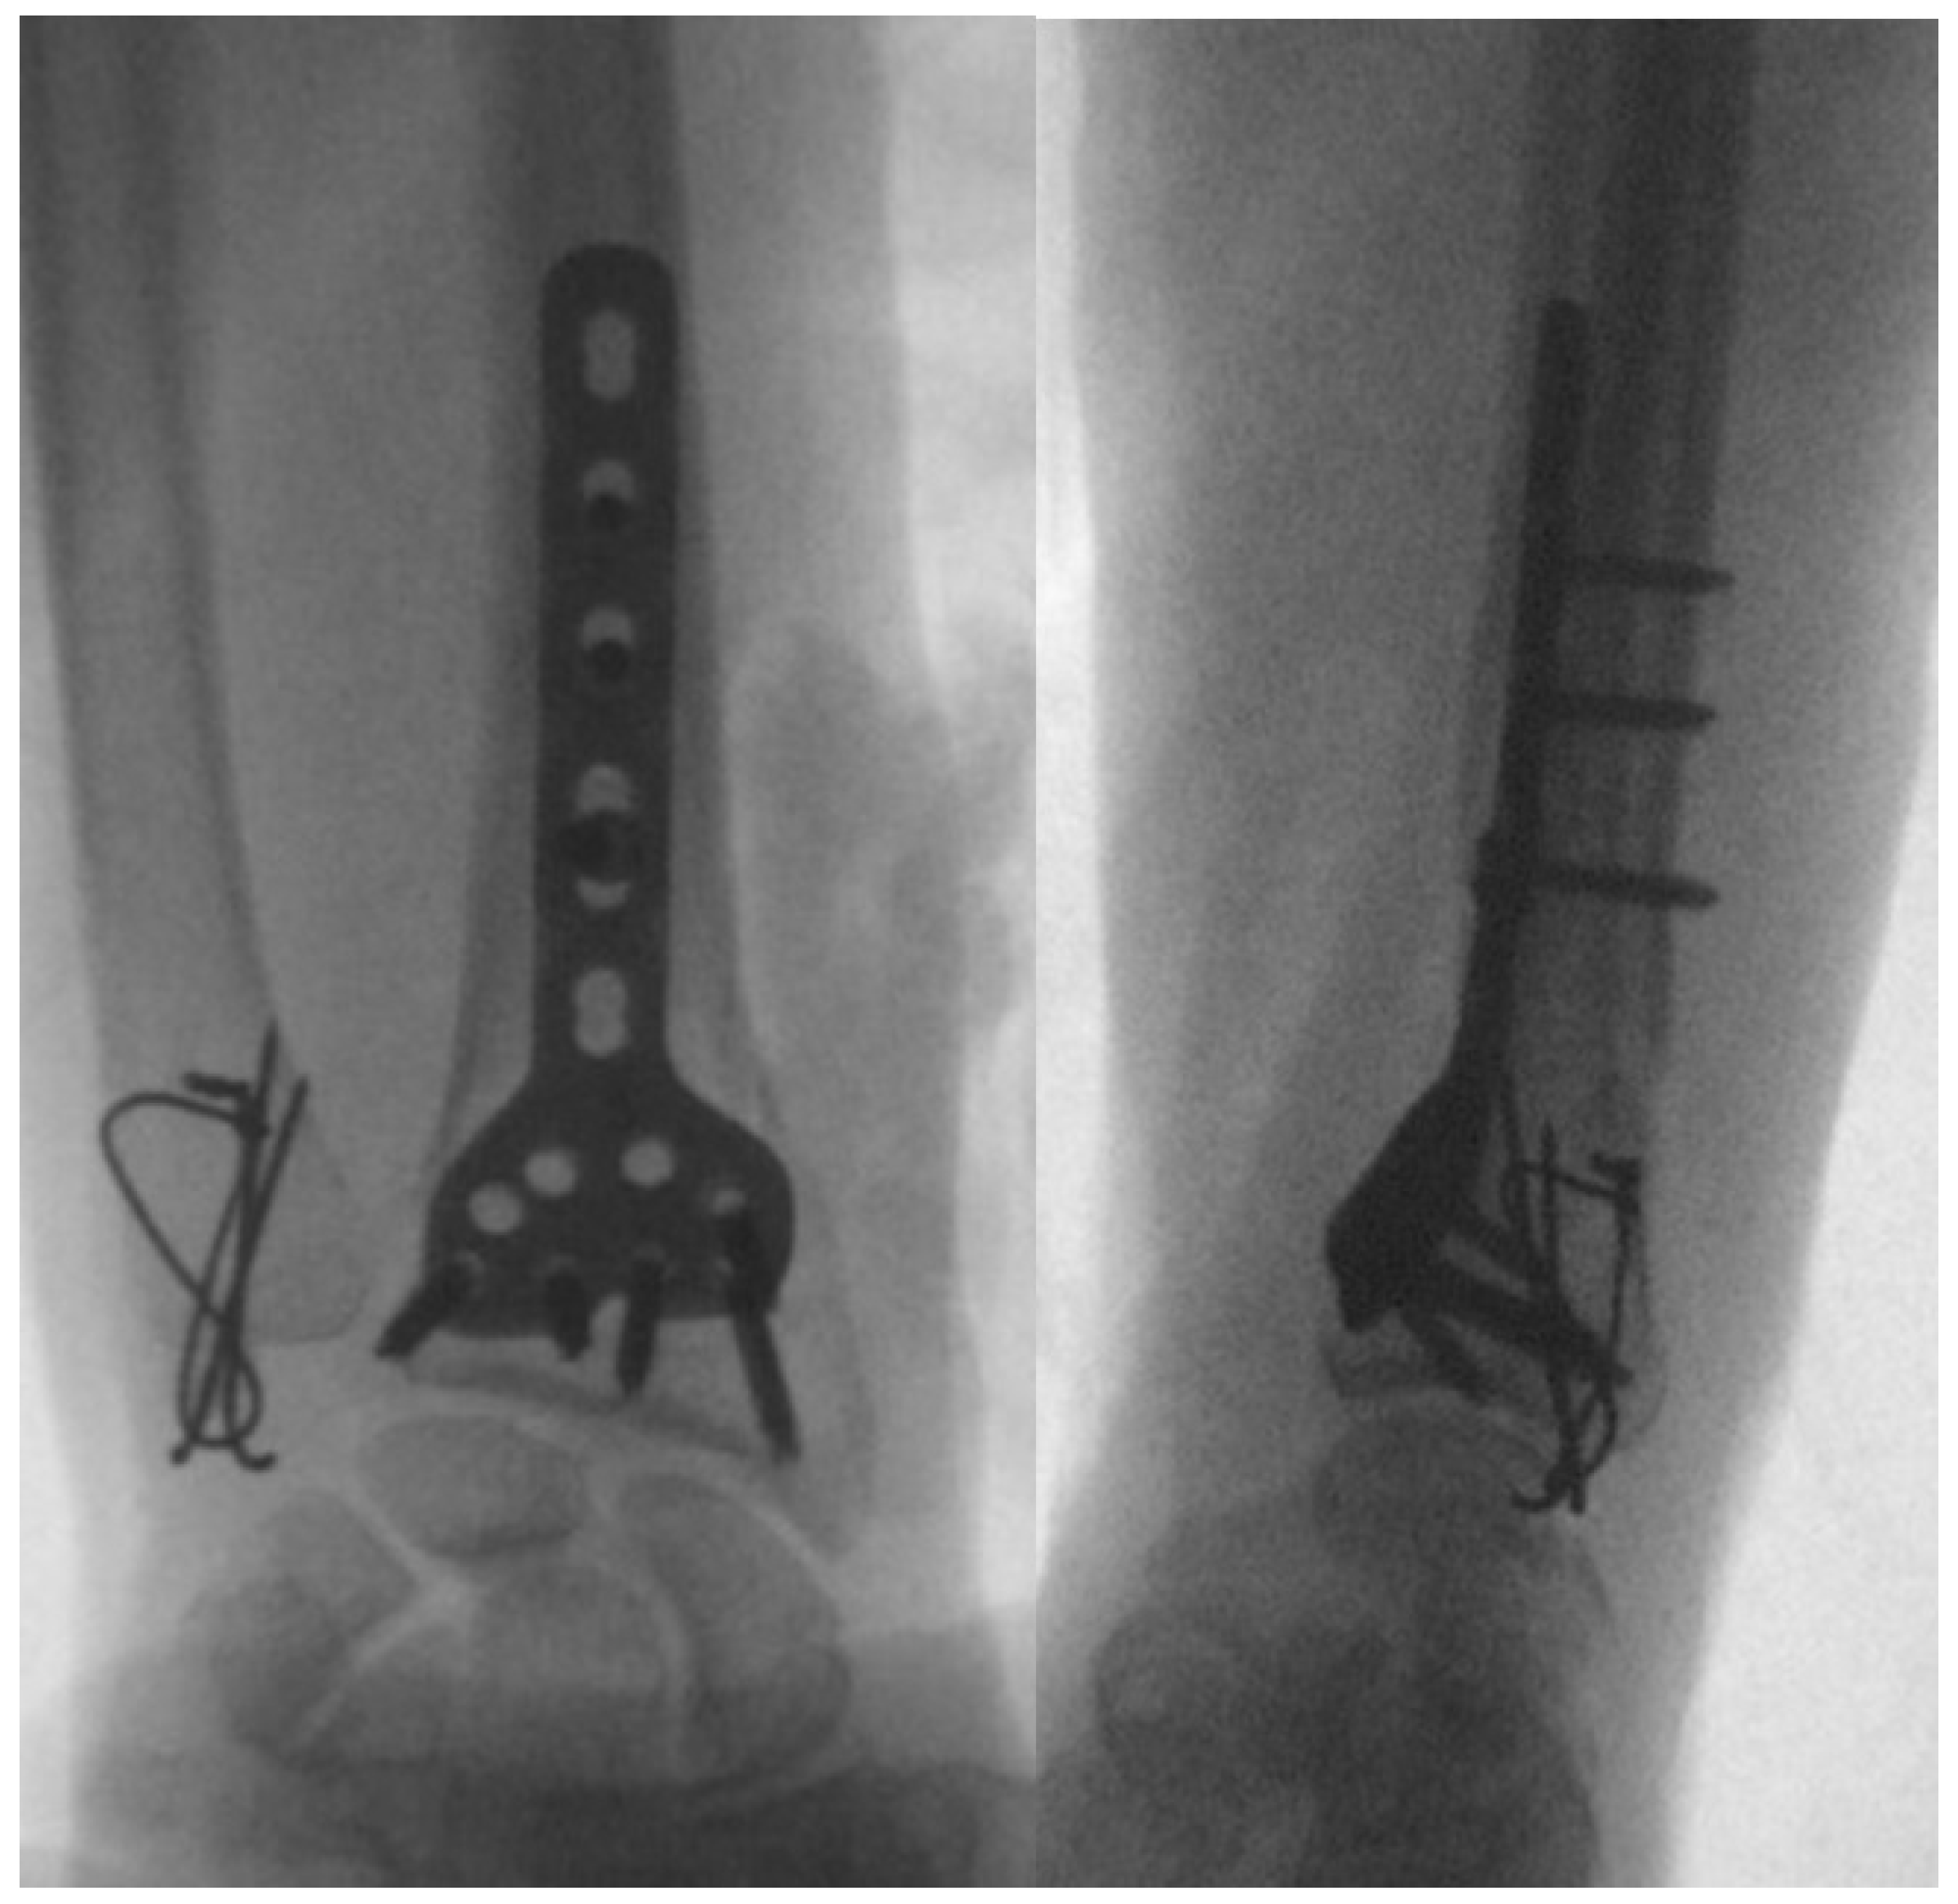

| Galeazzi fractures | High-energy trauma | Clinical presentation: forearm swelling, deformity [60]. Imaging: X-rays, CT scans [7]. | Surgical intervention: ORIF, DRUJ stabilization [7,65,66], postoperative care and rehabilitation. Complications may include persistent pain, stiffness, instability [60]. | Comprises approximately 7% of all forearm fractures [61]. |

5.1. Conventional Radiography